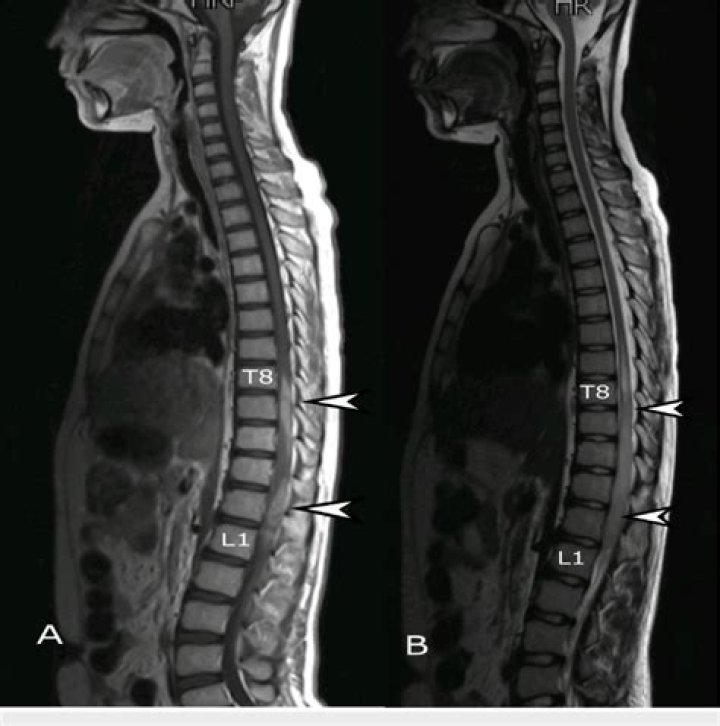

An MRI may be able to detect brain activity connected to fibromyalgia pain. For patients dealing with fibromyalgia, the widespread musculoskeletal pain they feel is made worse by the frustration and misunderstanding that usually accompanies the disorder.